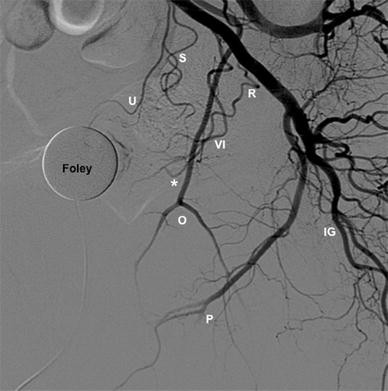

Prostatic Arterial Supply Anatomic And Imaging Findings Relevant For Selective Arterial Embolization Journal Of Vascular And Interventional Radiology

It secretes a thin, slightly alkaline fluid that forms a portion of the seminal fluid. Internal iliac artery (iia) anatomy. The prostate gland is the largest accessory gland of the male reproductive system. This artery enters the prostate at right angles to supply the glandular tissue.